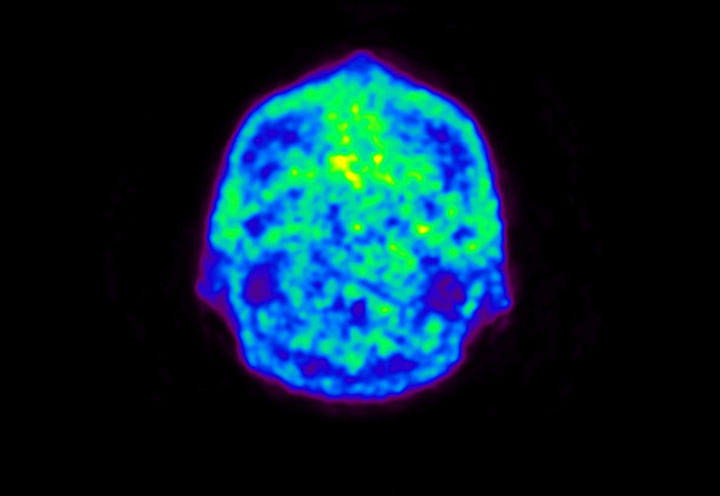

Head / Case5 : Amyloid

Axial

Courtesy : Kindai University Hospital

- Imaging protocol

- Injected dose: 4.27 MBq/kg, 18F-Flutemetamol

- Uptake time: 99 minutes

- Scan time: 20 minutes